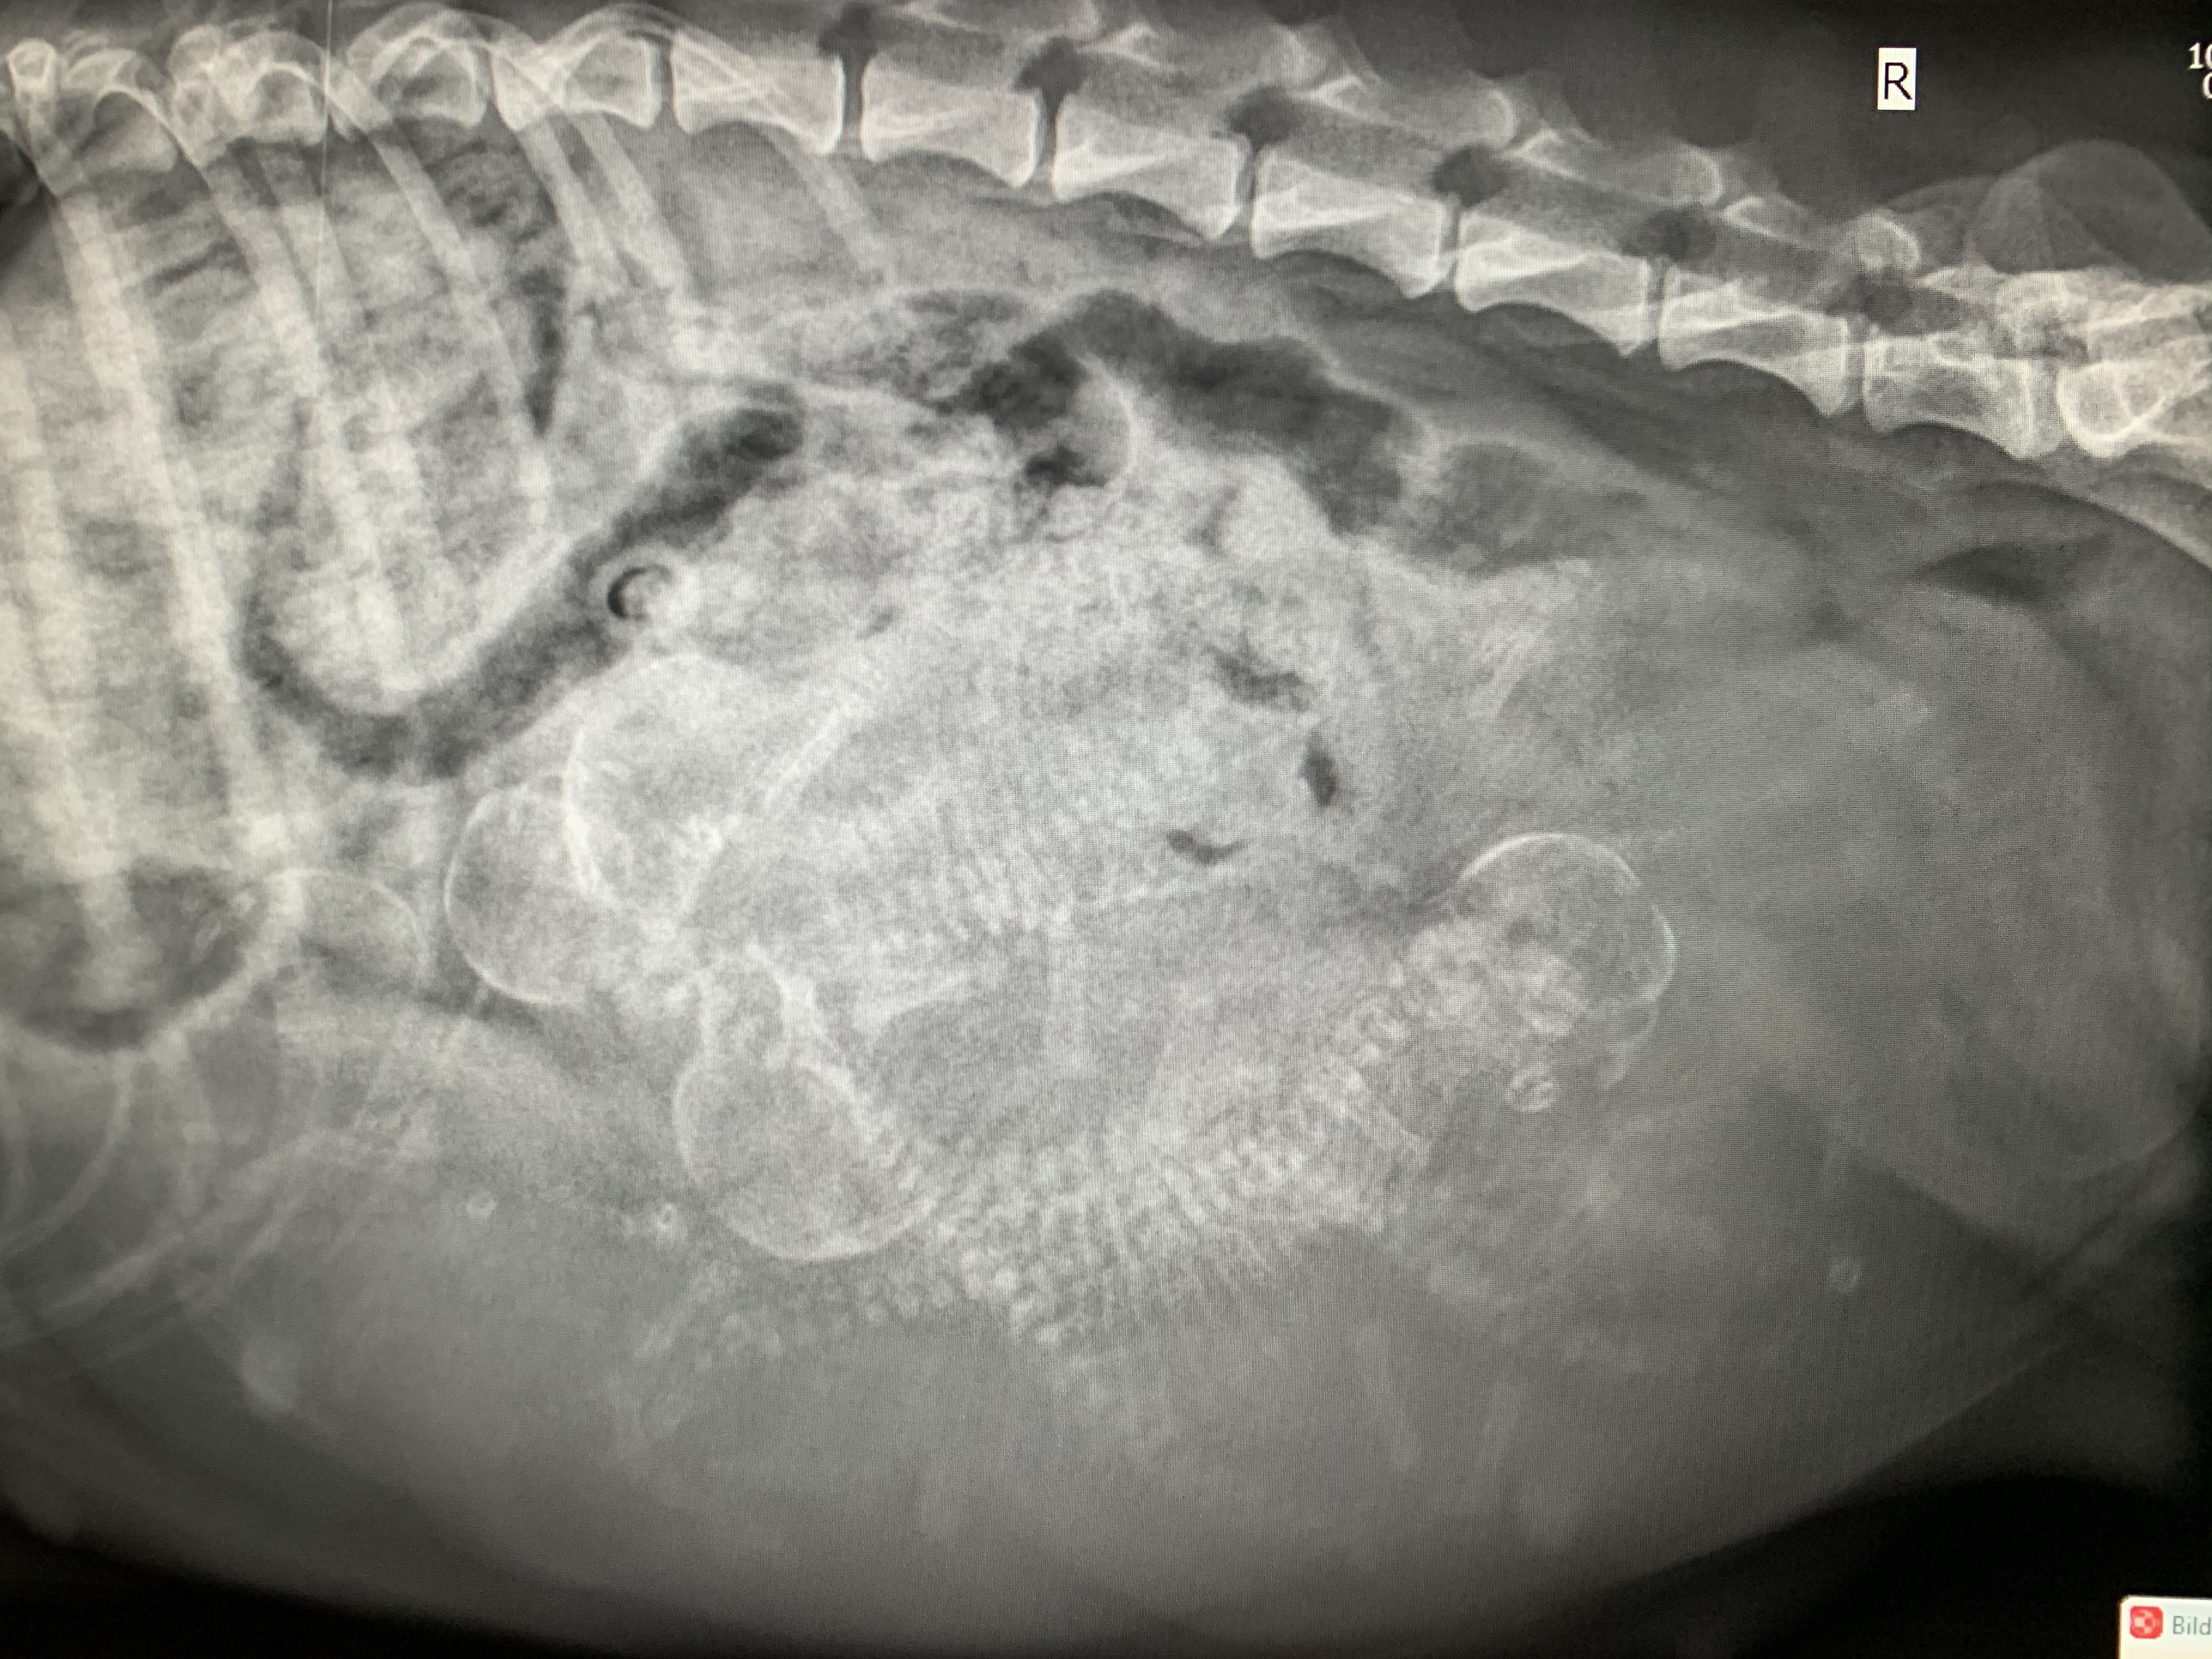

Hier noch ein paar Eckdaten zu den Mamas von heute :-). Wer von den beiden dann nun final unseren W oder X Wurf zur Welt bringt, werden wir bald wissen. Und damit ihr alle auch was zu tun habt, könnt ihr gerne mal Zählen - ich habe bewußt die Anzahl Welpen hier nicht mit angegeben. Mit den Bildern verabschieden wir uns dann mal bis nach der Geburt von W und X Wurf .......

Chili - Tag 54 - + 4,5 Kg somit aktuell 21,35 kg